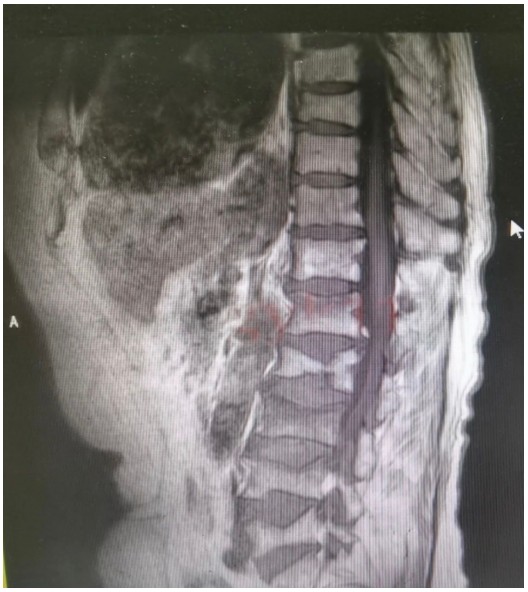

原來,89歲的占大爺因在家勞作時突發(fā)腰背部疼痛難忍、腰部無法直立,行走困難,在家臥床休息兩周后疼痛仍未減輕,于是來到衡陽市中心醫(yī)院脊柱外科就診。接診的盛凱醫(yī)師仔細查體結合磁共振檢查發(fā)現(xiàn),占大爺腰椎L1、L3、L4有椎體壓縮骨折,診斷為腰椎體壓縮骨折、重度骨質疏松癥。錢軍博士團隊結合對病人多椎體的骨折做出了細致的評估,經(jīng)過認真分析研究,決定為患者實施腰椎體壓縮性骨折經(jīng)皮穿刺椎體成形術(PVP)。手術當天,醫(yī)師團隊在C-臂監(jiān)視器透視下,分別定位L1、L3、L4雙側椎弓根位置,以標記穿刺點為中心做3mm切開,在透視下注入骨水泥,再次透視見骨水泥位置良好,順利完成手術。

據(jù)悉,該手術經(jīng)皮透視下穿刺,手術切口小,創(chuàng)傷小,無需縫合,微創(chuàng)手術皮膚切口僅2-3毫米,僅僅一個穿刺針的長度,通過穿刺針注入骨水泥,骨水泥可以達到穩(wěn)定椎體骨折、恢復椎體力學強度、防止椎體進一步壓縮和緩解疼痛的目標,使患者早期恢復正?;顒?。優(yōu)點為創(chuàng)傷小,臥床時間短,花費少。對于老年人椎體骨折微創(chuàng)下椎體成形術為最適宜該患者的治療方法。術后患者即感腰部疼痛明顯減輕,第二天可下床行走,已無腰痛不適,如此快速地恢復讓患者占大爺非常高興,自己再也不會受腰痛折磨整日與床為伴了,當即給脊柱外科團隊送上了錦旗表示感謝。